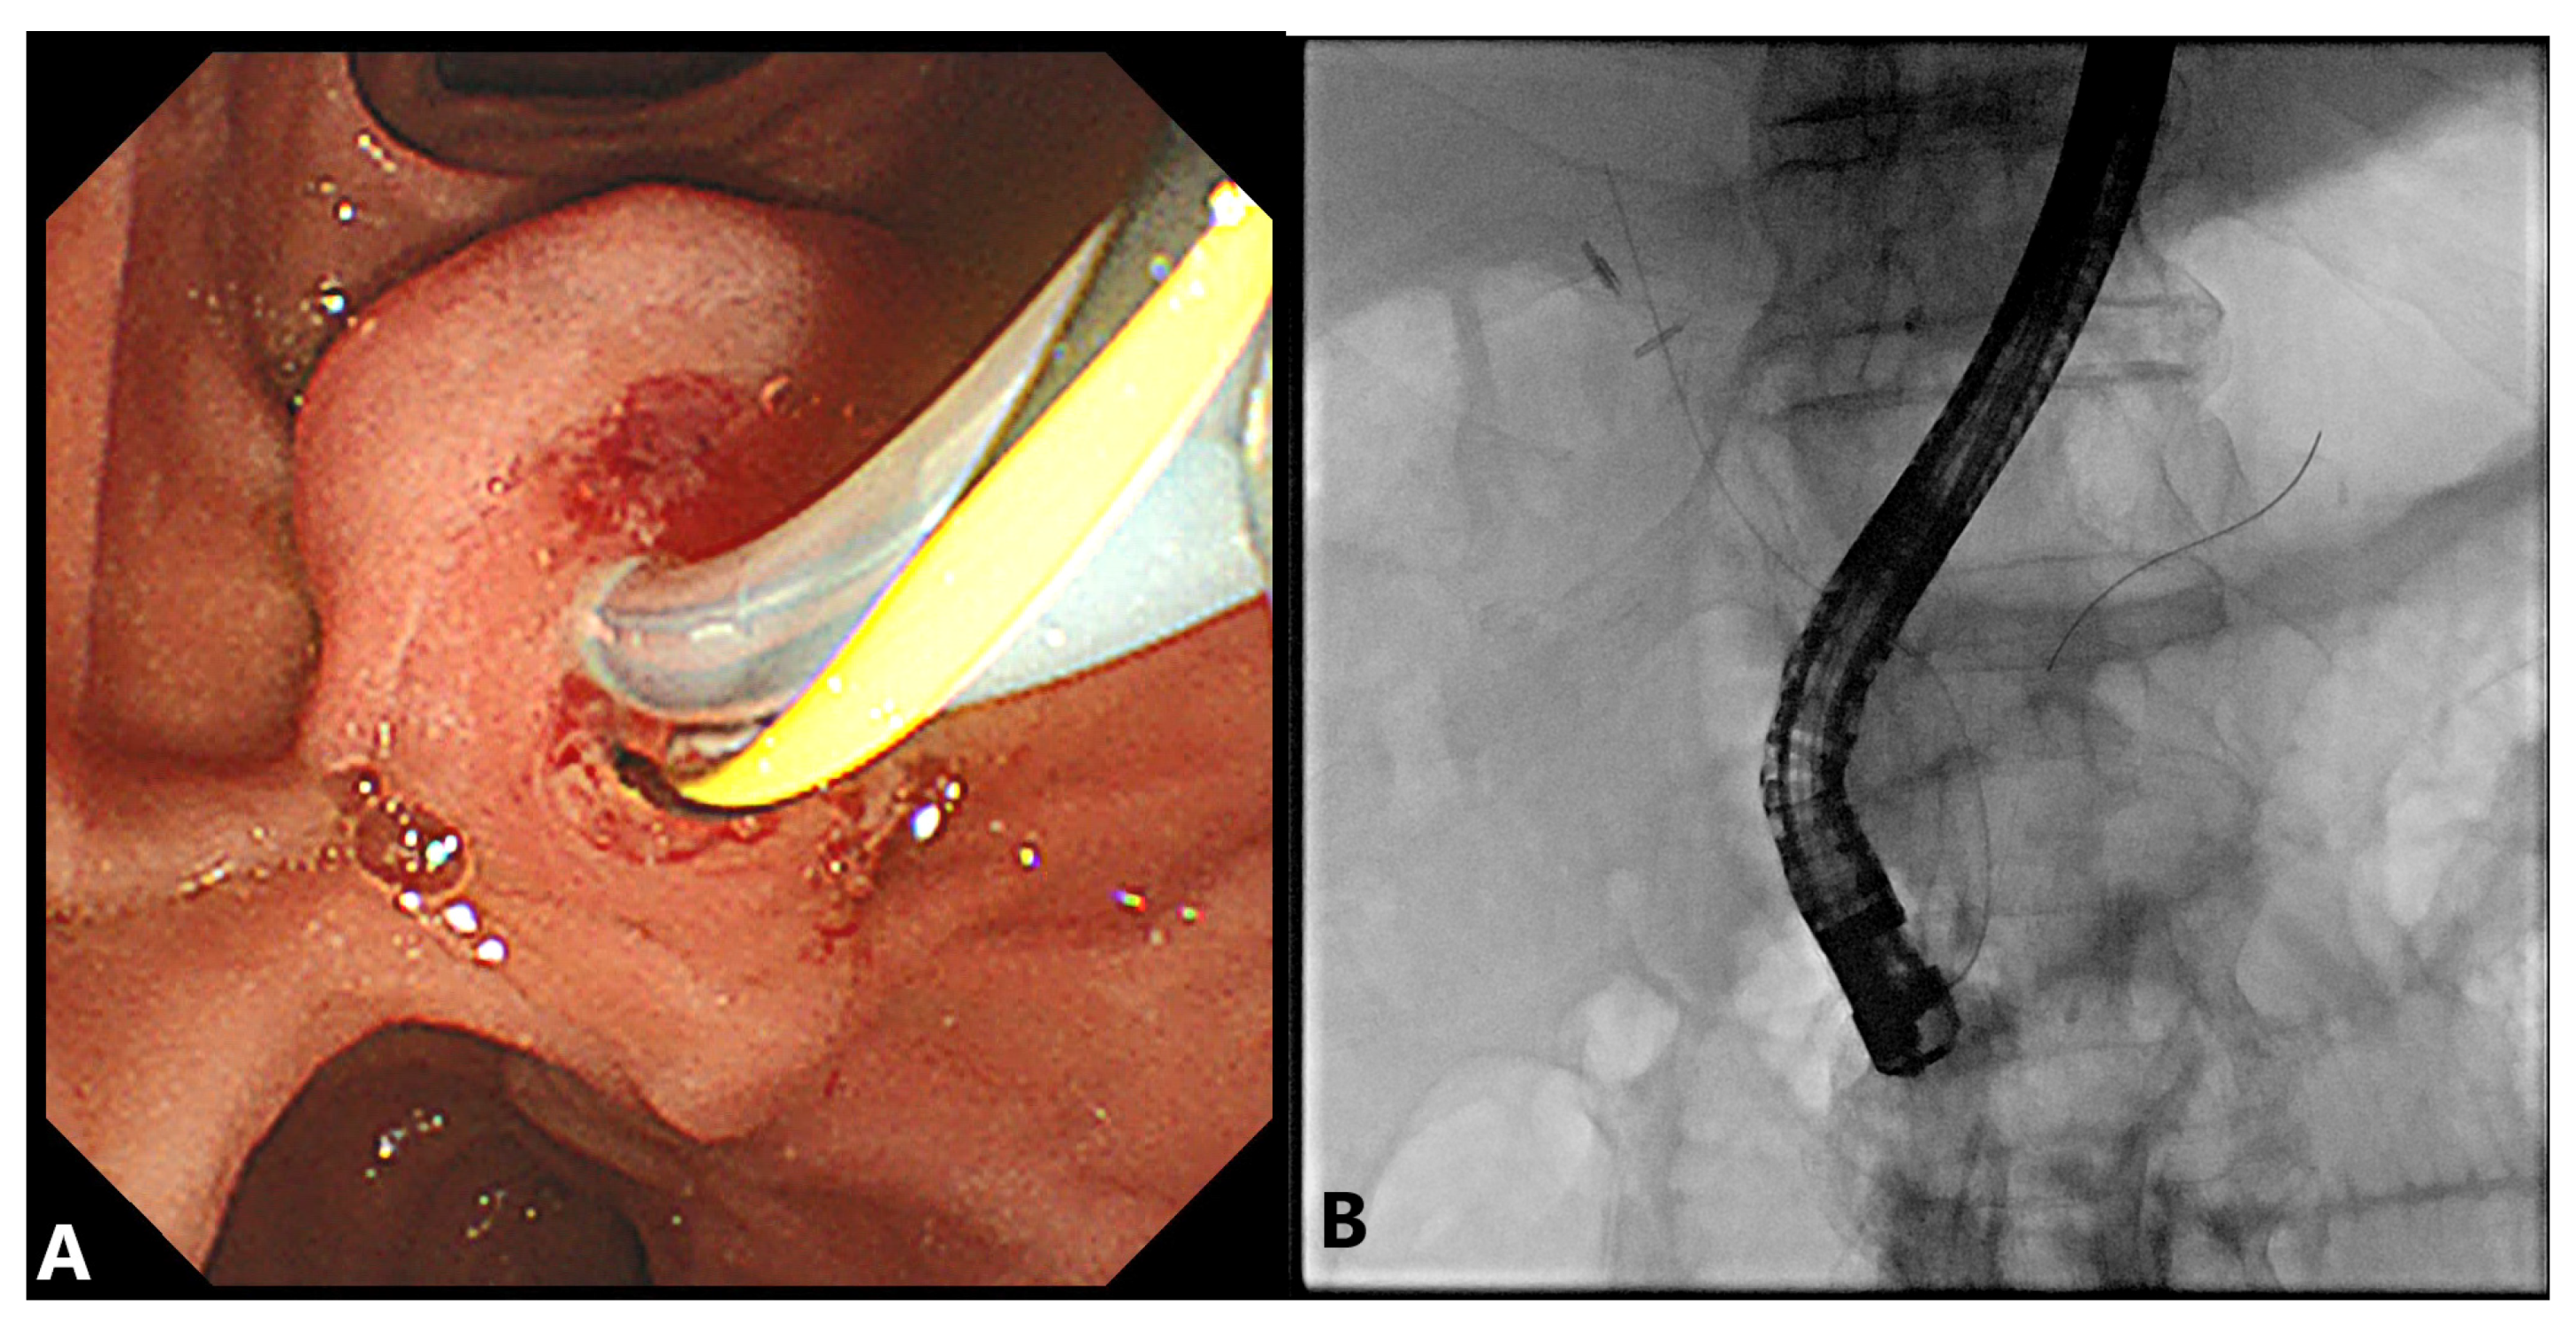

2.1. Double-Guidewire (DGW) Technique with or without Pancreatic Stenting

2.2. Precut Papillotomy